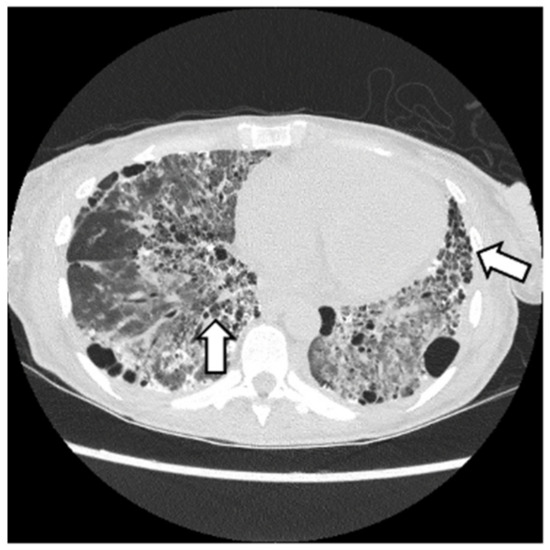

6.2. Histopathologic and Radiographic Findings in Myositis-Associated ILD